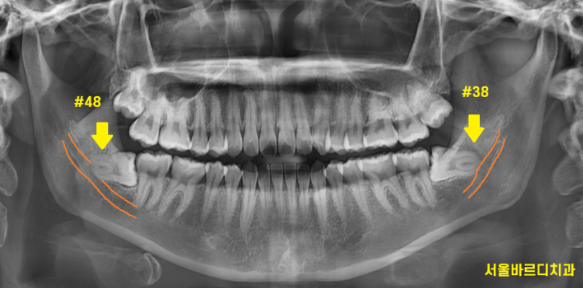

환자분은 위아래 4개의 사랑니를 모두 가지고 계셨습니다.

잇몸이 붓고 불편한 부분은

아래 사랑니였습니다.

모양이 누워있죠??

잇몸 안에 숨어있는 것이

"매복 사랑니"네요.